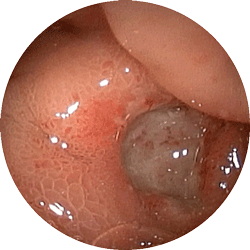

胃潰瘍2

胃潰瘍

心窩部の重い感じで来院

内服薬1ヶ月で治癒